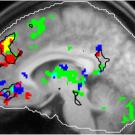

This fMRI brain scan shows areas that respond to familiar tunes, salient memories and music that is perceived as enjoyable.

MUSIC AND MEMORIES: Scientist finds region in the brain where golden oldies trigger emotion

Image: scan of brain with colored areas in various places

Study Finds Brain Hub That Links Music, Memory and Emotion